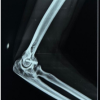

How to Cite This Article: Shah K A, Desai M M, Kantanavar R, Shah S. Complete Extra-articular Ankylosis of Hip and Stiff Elbow in a Case of Extensive Myositis Ossificans: A Rare Presentation. Journal of Orthopaedic Case Reports 2020 January, 10(01): 74-77.